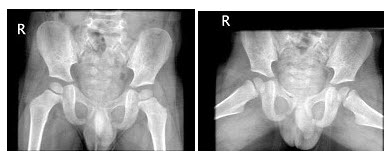

62、单项选择题

患者女,6岁,左下肢跛行三年,直立时臀部后耸,结合骨盆平片,正确的诊断是()

63、单项选择题

男,32岁,因车祸致右髋关节肿痛,活动受限摄片如图示,最可能的诊断是()